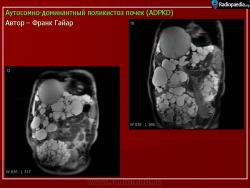

Аутосомно доминантный и аутосомно рецессивный поликистоз почек

ID: 16777 Autosomal dominant polycystic kidney disease Dr Frank Gaillard - 19 Feb 2012 Typical appearances of autosomal dominant polycystic kidney disease (ADP...

ID: 5203 ADPCKD - CT Dr Frank Gaillard - 17 Dec 2008 CT of the abdomen (coronal reformats) demonstrates both kidneys to be ma...

ID: 5202 ADPCKD - MRI Dr Frank Gaillard - 17 Dec 2008 Autosomal dominant polycystic kidney disease with extensive hepatic invo...

ID: 9719 ADPKD - gross pathology Dr Frank Gaillard - 15 May 2010 Autopsy specimen of bilateral ADPKD Original file: http://phil.cd...

ID: 10978 ADPKD with extensive hepatic involvement Dr Frank Gaillard - 6 Oct 2010 CT demonstrates markedly enlarged kidneys with numerous cysts, some of w...